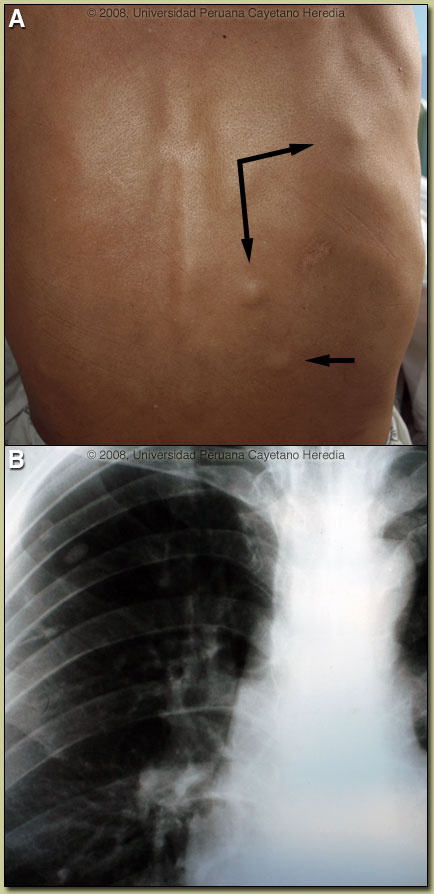

| Diagnosis: Neurocysticercosis due to Taenia solium. Cysticerci in soft tissue. |

Discussion: X-ray examination of the lower extremities [Image C] disclosed multiple linear cigar-shaped soft-tissue calcifications that are diagnostic of cysticercosis. The calcified cysticercus produces single (rarely) or multiple (often several hundred) calcifications in the soft tissues, which are linear or oval in shape and usually measure 4-10 mm or more in length and 2-5 mm in width. Cysts as large as 23 mm have been reported. The calcified cysts will have their long axes in the plane of the surrounding muscle bundle. No other organism results in a calcification pattern like this. On further review of the Chest X-ray all the calcifications were found to be extra-thoracic and in the soft tissues [Image D].